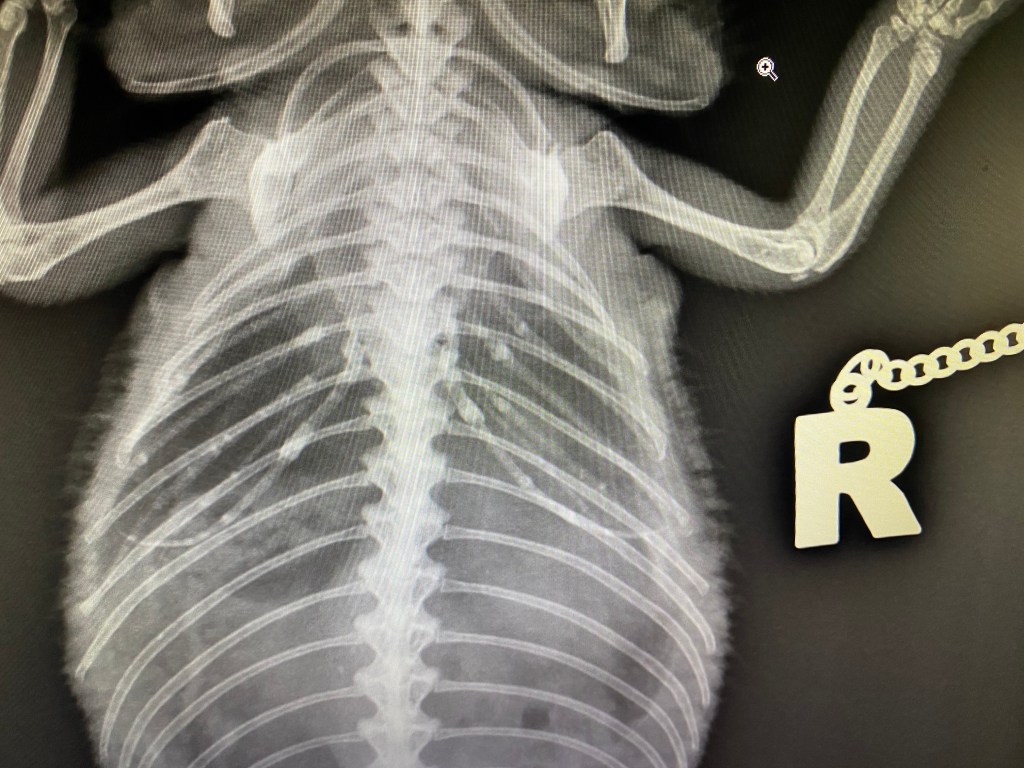

This was followed by morning consults and operations. The practice was very well organized and very clean, but lacked an anesthetic machine, X-Ray equipment and an endoscope, which made some procedures quite challenging.